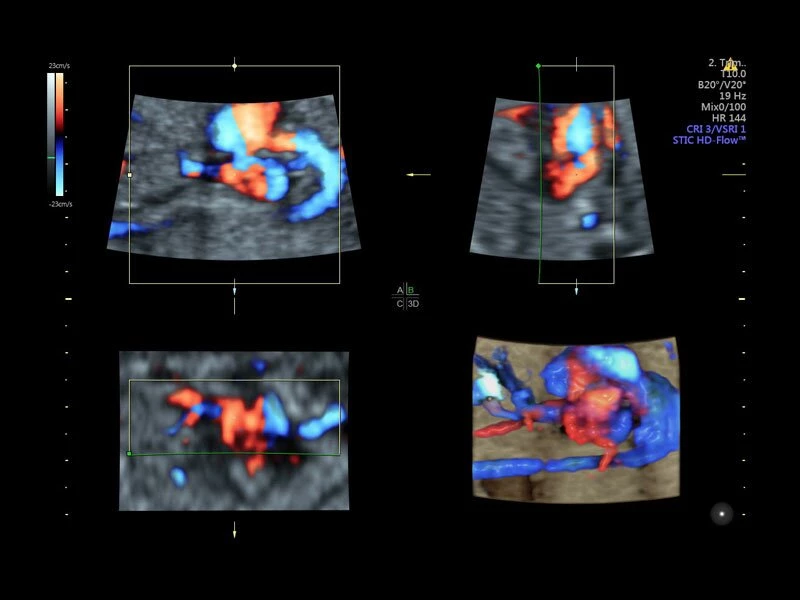

Объемное сканирование Voluson — 3D/4D вашей мечты

Объемное УЗИ на Voluson E10 — это не просто потрясающе красивая картинка, это ценный инструмент получения дополнительной информации при обследовании женщин.

Voluson E10 поддерживает инновационные технологии формирования изображений — HDlive Silhouette и HDlive Flow, которые позволяют увидеть мельчайшие детали. Алгоритм SonoRenderlive упрощает рабочий процесс и дает возможность реконструировать изображение поверхностей, определяя область перехода между тканью и жидкостью.

- HDlive

Инновационная технология визуализации HDlive обеспечивает получение реалистических изображений за счет эффекта объемного зрения, повышая достоверность клинической оценки. Теперь режим HDlive дополняют две новые функции:

- Технология HDlive Silhouette — задает разный уровень прозрачности, помогая выявлять контуры внутренних структур и точнее оценивать состояние плода в первом триместре.

- Технология HDlive Flow — повышает реалистичность визуализации сосудистых структур, улучшая восприятие глубины (по сравнению с традиционным цветовым допплером и функцией HD-Flow).